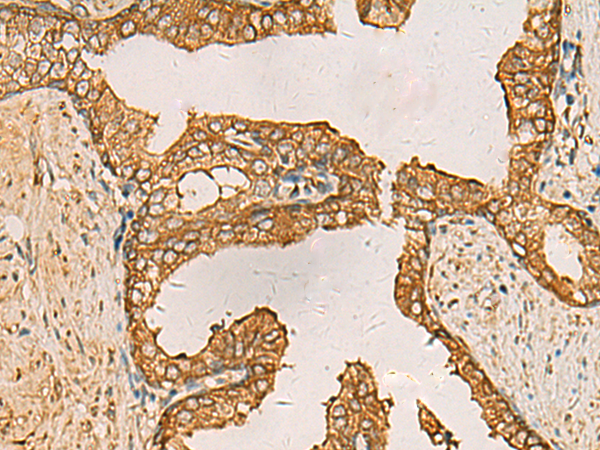

IHC positive control: |

Human liver cancer and Human prostate cancer |

IHC Recommend dilution: |

50-200 |